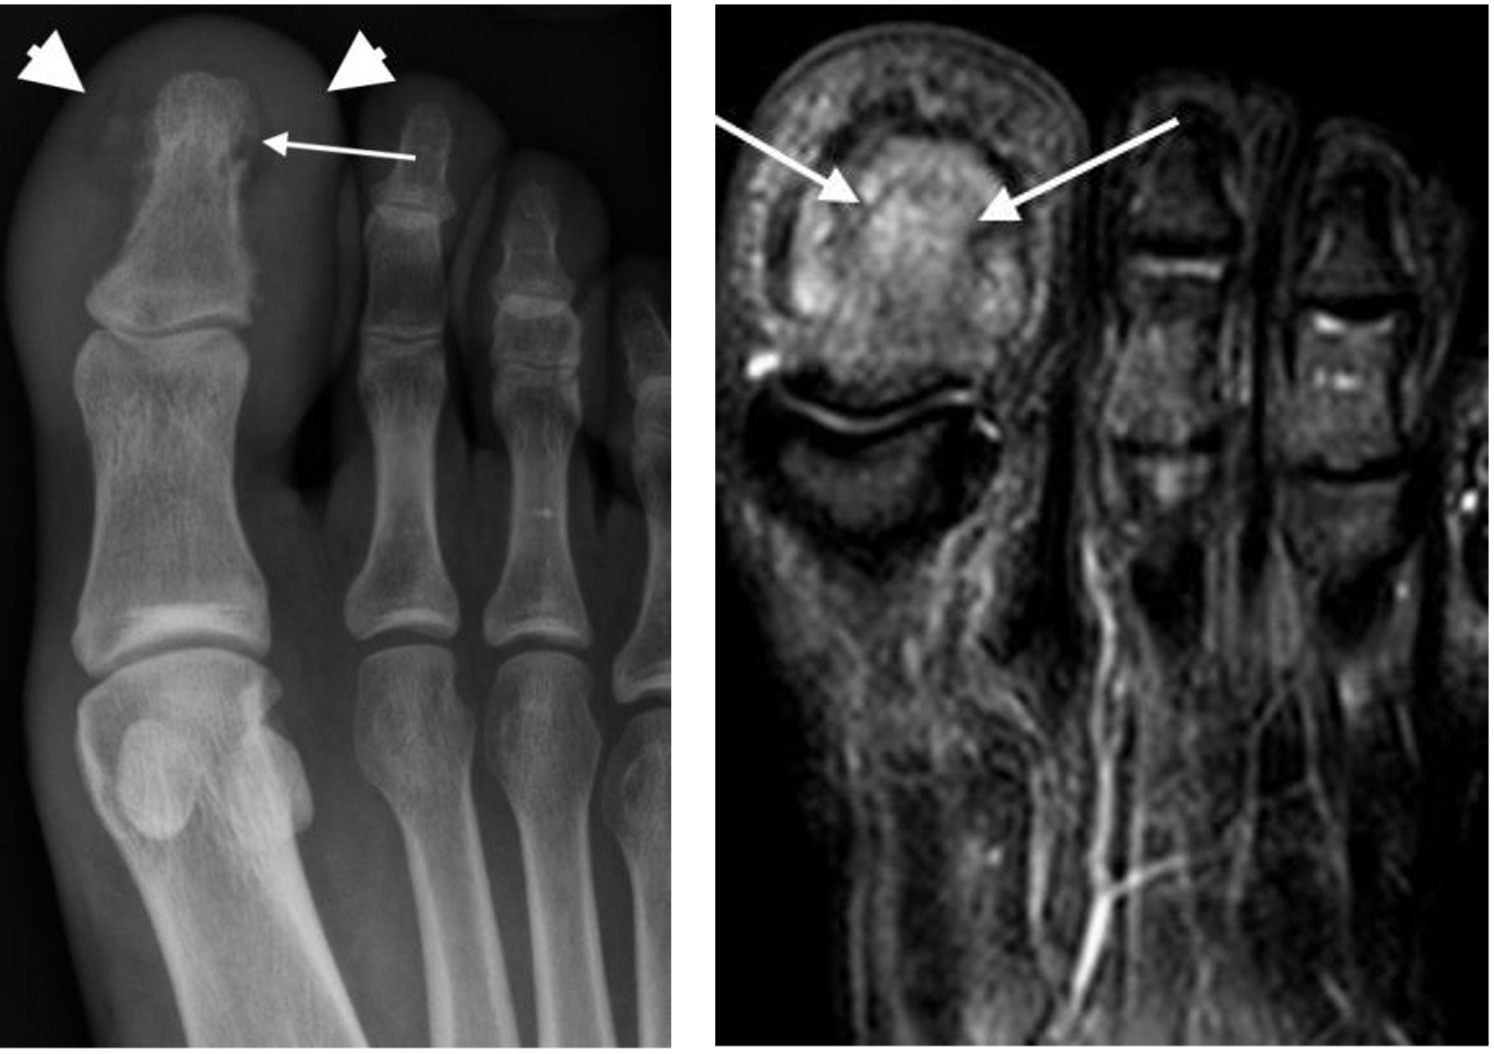

Osteomyelitis 1st toe distal phalanx with soft tissue swelling (arrowheads), osteolysis (arrow), periostitis and increased signal on STIR (fluid-sensitive) MRI

Freiberg’s disease with flattening and sclerosis of the 2nd metatarsal head (arrow)